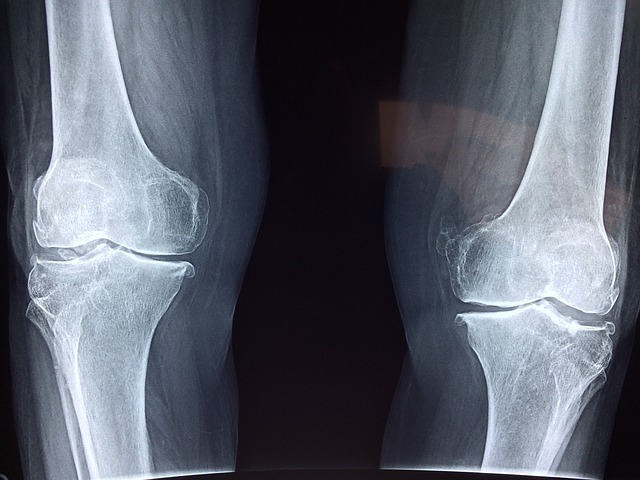

건강한 무릎은 우리 일상생활에서 핵심적인 역할을 합니다. 하지만 오랜 시간 동안 잘못된 자세나 부정확한 운동으로 인해 무릎에 스트레스가 가해질 수 있습니다. 다행히도, 올바른 식습관을 통해 무릎 건강을 유지하고 강화할 수 있는 방법이 있습니다. 이 글에서는 무릎 건강에 도움이 되는 다양한 식품에 대해 알아보겠습니다.

무릎 건강을 유지하는 핵심은 염증을 관리하는 것입니다. 염증은 무릎 주변의 조직에 손상을 줄 수 있으며, 만성적인 염증은 관절염과 같은 심각한 문제로 이어질 수 있습니다. 염증을 줄이는 데 도움이 되는 식품 중에는 오메가-3 지방산을 풍부하게 함유한 식품이 있습니다. 예를 들어, 연어, 고등어, 마른 견과류 등은 오메가-3을 풍부하게 함유하고 있어 염증을 감소시키는 데 도움이 됩니다. 또한, 과일과 채소 중에서는 파인애플과 블루베리 같은 과일, 녹색 잎채소가 염증을 줄이는 데 효과적입니다. 이러한 식품들을 적절히 섭취하여 무릎 주변의 염증을 관리할 수 있습니다. 염증은 무릎을 비롯한 다양한 부위에서 발생할 수 있는 문제로, 만성적인 경우에는 심각한 합병증을 유발할 수 있습니다. 따라서 염증을 줄이는데 도움이 되는 식품을 섭취하는 것이 중요합니다. 오메가-3 지방산이 풍부한 식품은 염증을 감소시키는 데 효과적입니다. 이는 연어, 고등어, 마른 견과류 등에서 찾을 수 있습니다. 또한, 과일과 채소 중에서는 파인애플과 블루베리가 염증을 줄이는 데 도움이 됩니다. 파인애플에는 소화 효소인 브로메린이 함유되어 있어 염증을 완화하고 소화를 촉진합니다. 블루베리는 항산화제와 염증을 줄이는 특성을 가지고 있어 무릎 건강에 도움이 됩니다. 이러한 염증을 줄이는 식품들을 적절히 조합하여 다양한 영양소를 공급하면서 건강한 식단을 유지할 수 있습니다.

근육을 강화하는 식품들을 적절히 조합하여 건강한 식단을 구성하는 것이 중요합니다. 단백질, 비타민 K, 마그네슘이 풍부하게 함유된 고기, 채소, 견과류 등을 포함한 식단은 근육을 강화하여 무릎 관절을 지지하고 보호하는 데 도움이 됩니다. 정기적인 운동과 함께 이러한 식품들을 섭취하여 건강한 근육을 유지하고 무릎 건강을 증진시키는 것이 중요합니다. 연골은 무릎 관절을 보호하고 충격을 흡수하는 중요한 조직입니다. 따라서 연골 건강을 증진시키는 식품을 섭취하는 것은 무릎 건강을 유지하는 데 중요합니다. 비타민 C는 연골의 주요 구성 성분인 콜라겐의 생성에 필수적입니다. 따라서 비타민 C가 풍부한 식품을 섭취하는 것이 연골 건강을 증진시키는 데 도움이 됩니다. 오렌지, 자몽, 파인애플과 같은 과일은 비타민 C가 풍부하게 함유되어 있어 이러한 과일을 섭취하여 연골의 건강을 지킬 수 있습니다. 또한, 비타민 D도 연골 건강을 유지하는 데 중요한 영양소입니다. 비타민 D는 칼슘 흡수를 촉진하여 뼈와 연골의 건강을 지원합니다. 태양에서 비타민 D를 얻을 수 있지만, 현대인들은 태양에 노출되지 않는 경우가 많기 때문에 음식을 통해 비타민 D를 보충하는 것이 중요합니다. 우유, 요구르트, 살몽과 같은 식품은 비타민 D가 풍부하게 함유되어 있어 연골 건강을 유지하는 데 도움이 됩니다. 뿐만 아니라, 적절한 수분 섭취도 연골 건강을 유지하는 데 중요합니다. 연골은 수분을 포함한 피로부터 영양분을 흡수하여 건강을 유지합니다. 따라서 충분한 수분을 섭취하여 몸 내 수분을 유지하는 것이 중요합니다. 물뿐만 아니라, 채소와 과일에도 수분이 풍부하게 함유되어 있으므로 이러한 식품들을 섭취하여 수분을 보충할 수 있습니다. 연골 건강을 증진시키는 식품들을 적절히 조합하여 다양한 영양소를 공급하면서 건강한 식단을 구성하는 것이 중요합니다. 비타민 C와 비타민 D가 풍부하게 함유된 과일, 채소, 유제품 등을 포함한 건강한 식단은 무릎의 연골을 보호하고 건강을 유지하는 데 도움이 됩니다.

무릎 건강은 우리의 삶의 질과 움직임의 자유에 큰 영향을 미칩니다. 올바른 식습관은 무릎 건강을 유지하고 강화하는 데 중요한 역할을 합니다. 염증을 줄이고 연골을 보호하며 근육을 강화하는 식품들을 포함한 건강한 식단은 무릎 건강을 증진시키고 무릎 관절에 대한 부담을 줄일 수 있습니다. 이러한 식습관을 통해 우리는 무릎 건강을 지속적으로 유지하고, 더 나은 삶의 질을 누릴 수 있습니다